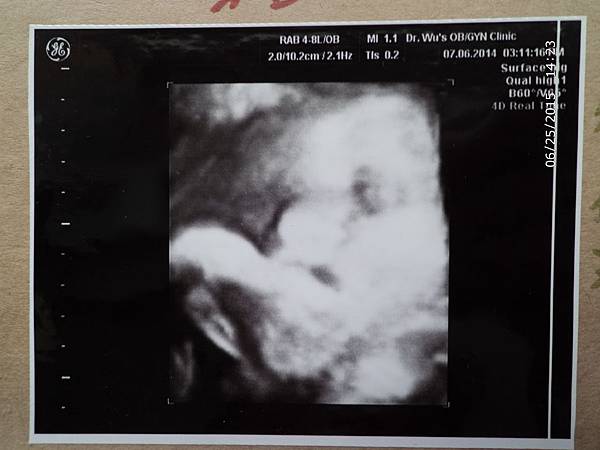

【孕期】小Abby好萌啊~~(乙型鏈球菌)